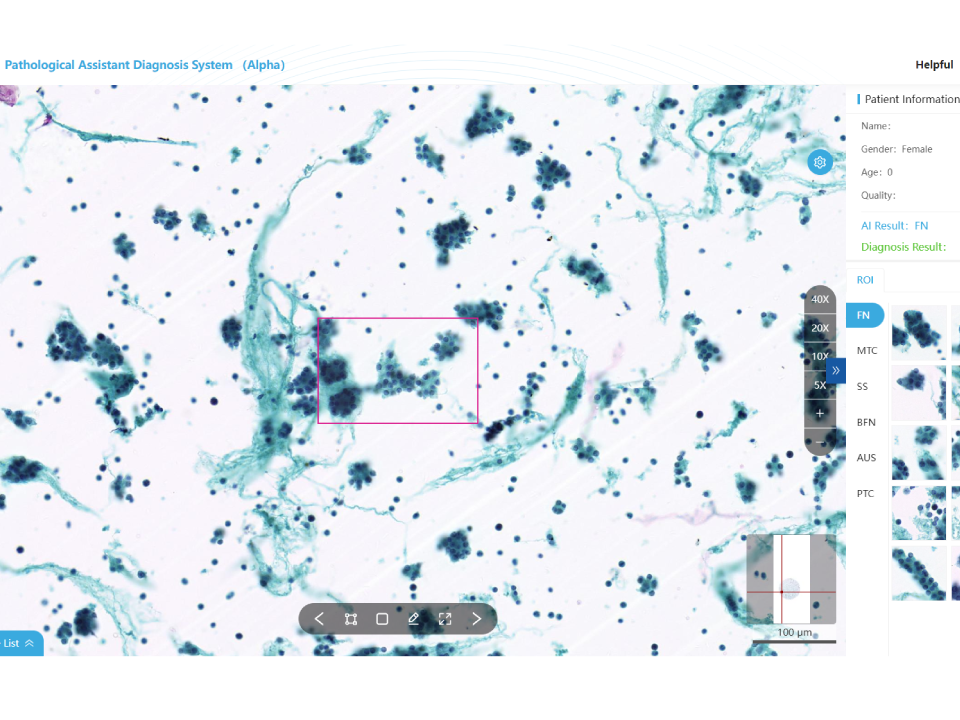

Thyroid Cytology Assistant Diagnostic Module

Automatic recognition of 6 cell types. High-speed analysis for improved efficiency. Validated by multi-center clinical trials: sensitivity ≥ 95%, specificity ≥ 90%. Whole slide analysis to reduce misdiagnosis TBS standardized pathology reports.

Thyroid Cytology Assistant Diagnostic Module

- Automatic recognition of 6 cell types.

- High-speed analysis for improved efficiency.

- Validated by multi-center clinical trials: sensitivity ≥ 95%, specificity ≥ 90%.

- Whole slide analysis to reduce misdiagnosis TBS standardized pathology reports.